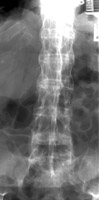

Anterior and lateral radiograph of the lumbar spine which reveals near complete fusion of all of the vertebral bodies. Spinal changes which include squaring of the vertebral bodies and fusion between adjacent levels. The fusion is secondary to syndesmophytes and resembles a bamboo stalk. This is most commonly found in ankylosing spondylitis.

AP spine - Click on the image for a larger versionALateral L-spine - Click on the image for a larger versionB